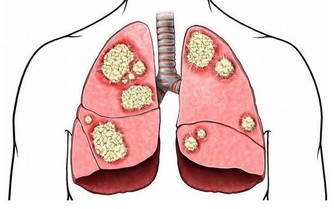

3、抗結核藥物

吡嗪酰胺和乙胺丁醇是熟知的抗結核藥,你如果看看藥物的使用說明書,裡面清楚的寫著,可能會導致尿酸增高。但是,很有意思的是,同樣作為抗結核藥物的利福平卻可以抑制尿酸的吸收,如果將這三種抗結核物質一起服用,並不會引起尿酸的過度升高。

4、免疫抑製劑

很多血液病的患者需要長時間的服用免疫抑製劑,而其中的環孢素、他克莫司能夠升高尿酸值,機制可能也與刺激近曲小管吸收尿酸相關。

5、抗腫瘤的藥物

環磷酰胺是非常常見的抗腫瘤藥物,它也能夠升高尿酸,容易產生高尿酸血症。